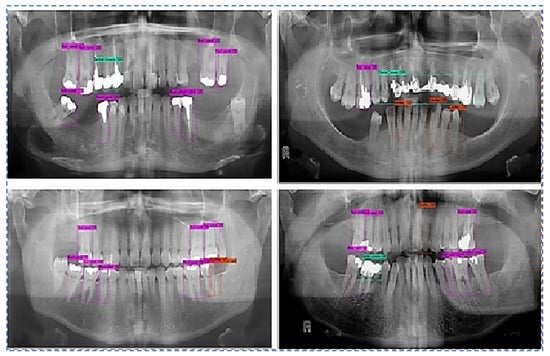

• Output Images using the best weight obtained for all teeth diseases are shown in Figure 8.

We augmented the data with image rotation and shear range, among other things, to reduce the overtraining effect. The average classification accuracy when using augmented training data was 99.33%. Compared to the result without data augmentation, data augmentation showed a noticeable improvement in classification accuracy. This suggests that expanding the dataset will result in further improvements. Unlike the previous methods, the proposed method achieves high classification accuracy. The comparative study of the proposed model with recent DL models is shown in Table 7.